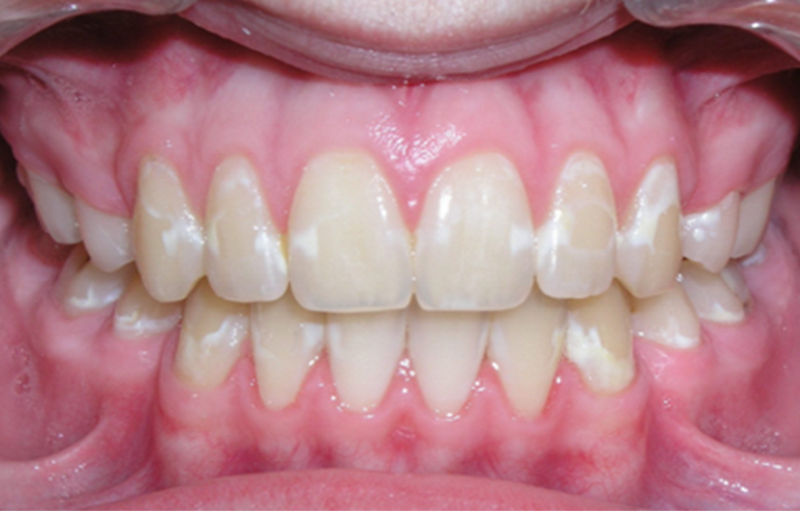

Initialkaries